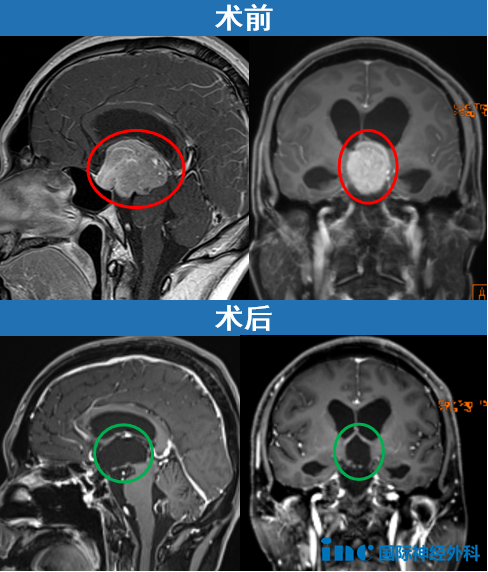

1.脑膜瘤:约1%颅内脑膜瘤起源于岩斜区,是岩斜区常见病变。它向上可侵犯岩骨尖、小脑幕、Meckel腔、鞍旁和海绵窦;向下侵犯内听道和颈静脉孔;向内侧达脑干和椎基底动脉。当肿瘤很大时,可包绕同侧Ⅲ~Ⅺ脑神经。患者临床可表现头痛、复杂的脑神经麻痹、共济失调等症状,严重者表现为偏瘫、认知功能障碍。目前,仍以手术切除为首选治疗方式。

示例1

示例2